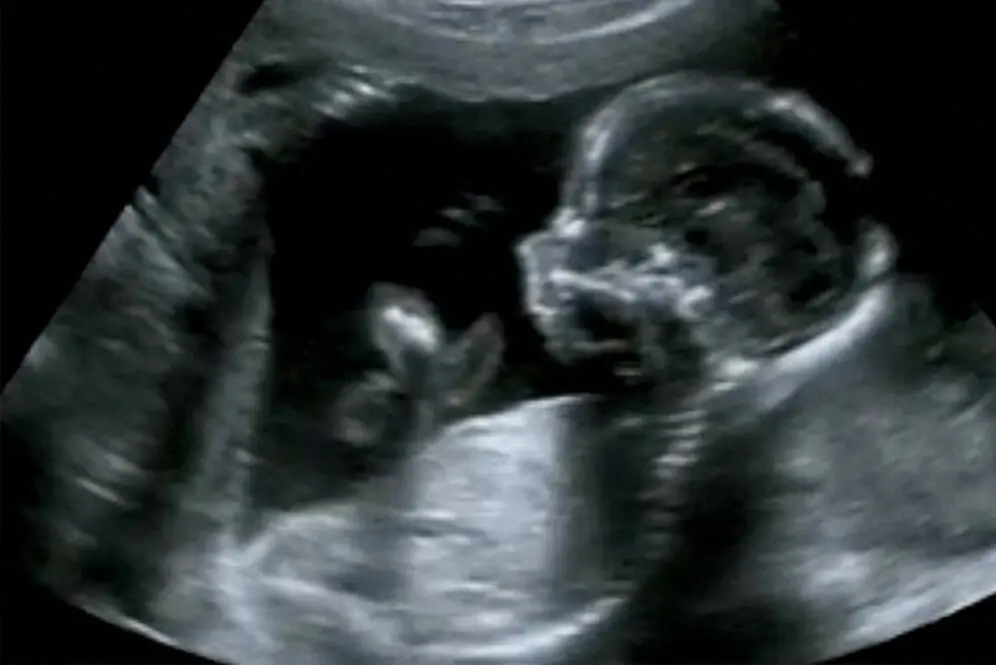

Wie wird die Nackenfaltenmessung durchgeführt?

Die Nackenfaltenmessung wird mit Hilfe eines Ultraschallgeräts durchgeführt. Der Arzt misst die Dicke der Flüssigkeitsansammlung im Nackenbereich des Feten. Die Messung erfolgt in Millimetern.